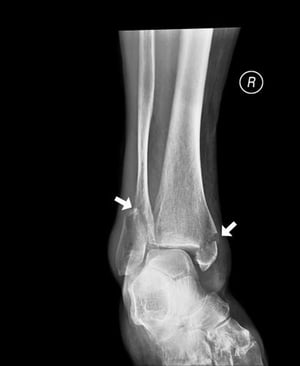

Frattura in entrambi i malleoli della caviglia

Questa frattura della caviglia coinvolge il malleolo mediale (della tibia) e il malleolo laterale (del perone).

SCIENCE PHOTO LIBRARY